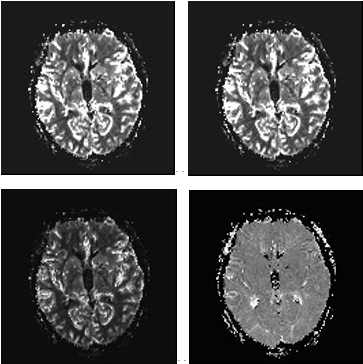

功能磁共振成像:是一种非侵入性反映活体脑的内部功能的检测方式。适用于脑特定区域与其功能之间的关系与对相关疾病脑区进行定位。包括弥散加权成像、灌注成像、弥散张量成像(DTI&DTT)和BOLD成像等。

其他包括血管成像技术(MRA)、水成像(MRCP)、全身弥散(DWI)、磁敏感成像(SWI)以及3D高分辨神经系统解剖成像等。